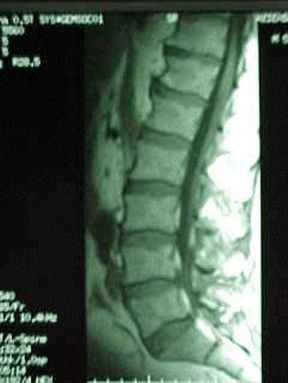

RMN spinale. Risonanza magnetica nucleare. La RMN della colonna vertebrale permette di evidenziare in dettaglio le strutture ossee e legamentose della colonna.